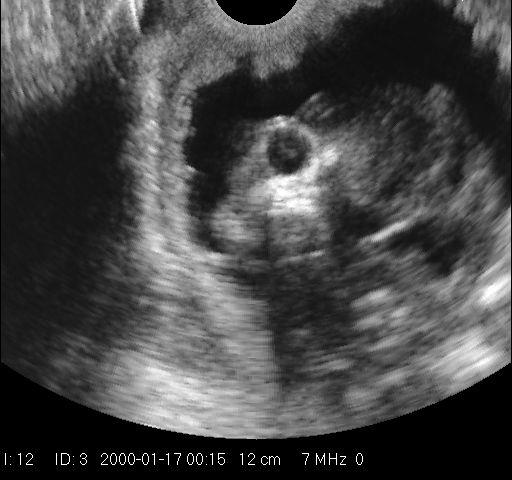

Catherine: One of the first ever successful images of pregnancy in miniature horses, captured by Dr Kowalski with the Draminski Animal Profi.

Nicola: How far along in her pregnancy was this catherine?

Catherine: Hi Nicola! This was at around 4 months.

Catherine: Thank you! We were pretty excited because there are very few (if any) reported successful scans of miniature horse pregnancies. They are too gassy to scan externally with ease, but too small to scan rectally. So to get this image was like winning the lottery.

Catherine: Hi Nicola - the best way would be like scanning a goat or sheep (from the side, under the leg). You have to try to find some little space through somewhere between all the air. It will be extremely difficult with a regular abdominal probe, but would love to see if you have any success. Don't feel down if you don't... getting this picture took about 3 hours and with four different machines!